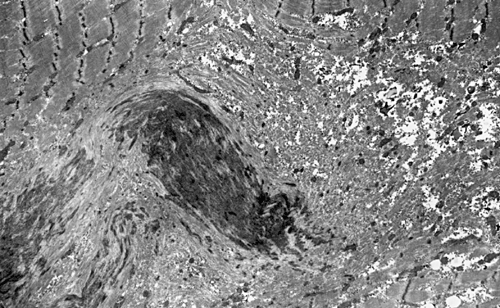

On hematoxylin-eosin stained sections, there is an increased variation of fiber diameter with many atrophic fibers intermingled with fibers of normal caliber. There is no evidence of fiber grouping or perifascicular atrophy. No inflammatory cells are present. There is also mild interstitial fibrosis (Panel A). On higher magnification, many fibers have a round concentric structure (Panel B). Irregular, centrally located depositions are also identified on modified Gomori's trichrome. The concentric nature, however, is not as obvious as in the hematoxin-eosin stained sections (Panel C). Type I and II fibers are not clearly separated in the ATPase preparation at pH 9.4. This is a common situation in chronically ill muscle (Panel D). The type I fibers are unusually dark. There is an increase in the proportion of type I fibers. The atrophic fibers are usually type II fibers. The concentric lesions are found predominantly in type I fibers (Panel E). There is an increase in PAS staining which is consistent with increased glycogen storage (Panel F). No increase in lipid content is demonstrated by oil red O (Panel G). On NADH-TR reaction, the concentric structures appear to have a clear central core that is devoid of enzymatic activity, a rim with intense enzymatic activity and a surround zone with relatively normal reactivity. These features are classic for target fibers (Panel H and I). No deficiency of laminin-2 (merosin) (Panel J) or dystrophin (Panel K) is demonstrated by immunohistochemistry. The central lesions are also immunoreactive for both laminin-2 and dystrophin. Immunohistochemistry for desmin demonstrate a core of strong immunoreactivity and also strong reaction in the sarcoplasmic membrane (Panel L and M). The target structures are also well demonstrated on semithin sections (Panel N). On electron microscopy, z-disc streaming is a common finding and they are often admixed with a substantial amount of dense granular electron dense substance (Panel O and P). There are also numerous cytoplasmic bodies characterized by radiating intermediate filaments (spheroid bodies) (Panel Q and R).

The two major pathologic findings are inclusion bodies and granulofilamentous material. Type I fibers are predominantly affected. Inclusions are eosinophilic on hematoxylin-eosin stain and bluish on modified Gomori’s trichrome stain. These inclusions are often negative for oxidative enzymes. A strong reactivity for desmin can be demonstrated by immunohistochemistry. The abnormal accumulation can occur as cytoplasmic inclusions, subsarcolemmal inclusions, spheroid bodies (10-20 mm oval or spherical inclusions), and patches or “hyaline structures”. In some cases, there is Z-disc streaming but no masses are demonstrated by trichrome stain. Numerous negative areas may be demonstrated by oxidative enzyme reactions. An accentuated intermyofibrillar network is seen by antidesmin antibody staining. Under the electron microscope, spheroid bodies appear as cytoplasmic bodies with a dense, granular core surrounded by fine filaments in a coronary arrangement. Although they are conspicuous on light microscopy, they may not be as distinctive at the ultrastructural level.

Granulofilamentous materials, also known as dappled dense structures” are dense anatomosing and trabeculated granular material that is about 100 nm in diameter is accumulated in between myofibrils or under the sarcolemma. The Z-disc streaming may appear contiguous to the granular deposits. They also appear as “non-hyaline” structure on immunofluroesent microscopy.Cytoplasmic bodies characterized by radiating intermediate filaments (spheroid bodies) are also common.